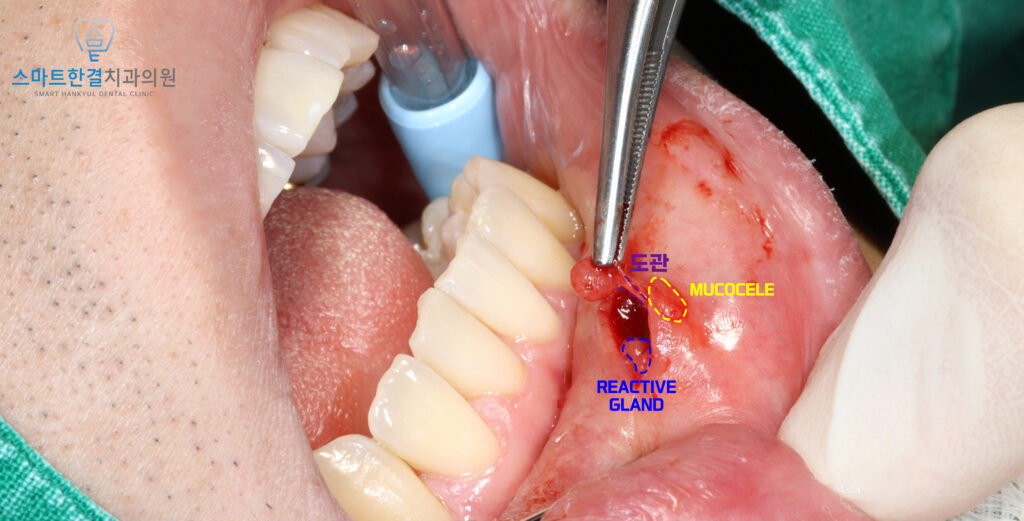

뮤코실이 있는 조직을 절개한 뒤,

반응성 소타액선과

뮤코실을 유발한 도관과 연결된

소타액선을 확인할 수 있었어요.

반응성 소타액선은

지속적인 자극과 염증으로 인해

비정상적으로 부풀어 있거나

변형된 상태의 침샘 조직으로,

뮤코실 형성을 반복시키는

원인이 될 수 있기 때문에

함께 제거해 주는 것이 중요해요.